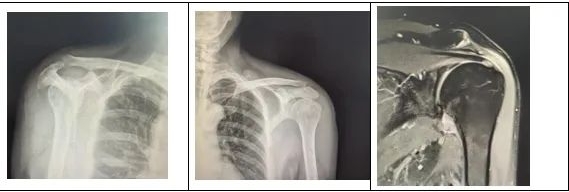

王先生的这两种肩关节疾病,治疗当中存在很大的冲突,冻结肩(肩周炎)需要在手术松解后尽早活动锻炼,而肩袖损伤需要在手术修补后进行一段时间的修养,在修养的这段时间里松解后的肩关节又会产生再次粘连的风险。

经过团队反复研讨,副主任医师李政为王先生实施了左肩关节松解术,肩袖锚钉缝合术,并在术中使用了双排锚钉。双排锚钉可以提供更强大的稳定性,可以使得肩关节在术后可以进行早期功能锻炼。该手术完美解决了治疗中的矛盾,整个手术过程不过两个小时。